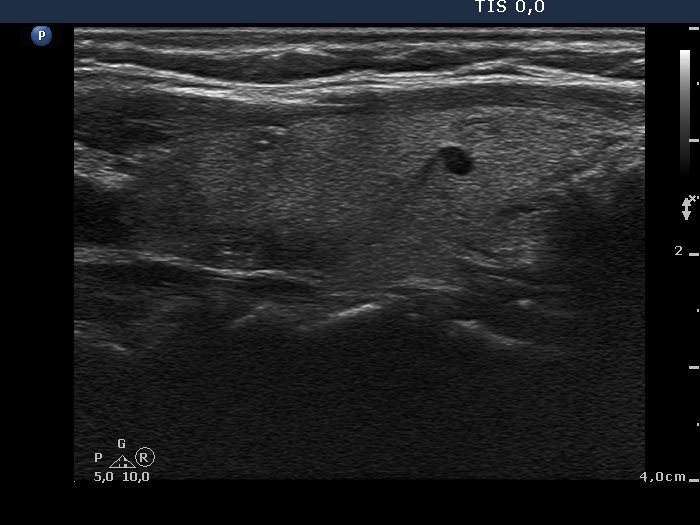

Subacute granulomatous thyroiditis - case 1777 (ultrasonographic picture 8)

Left lobe, longitudinal view. There are two, tiny discrete lesions presenting bright hyperechogenic granules and lines.